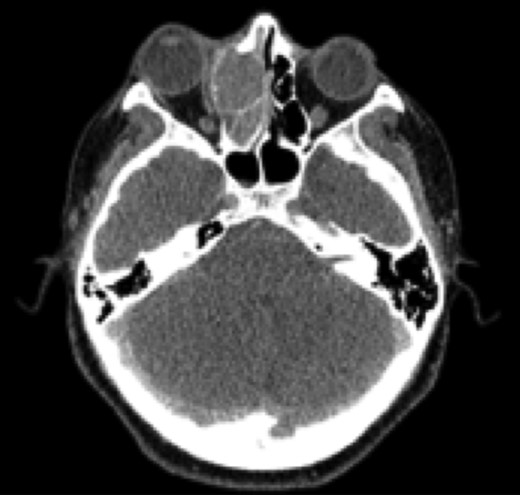

Paranasal sinuses CT showed a solid lesion located in middle, upper and common right meatus, ethmoid hemibody, with extension to lamina papyracea and lamina cribosa with superior oblique infiltration. (Fig. 1)